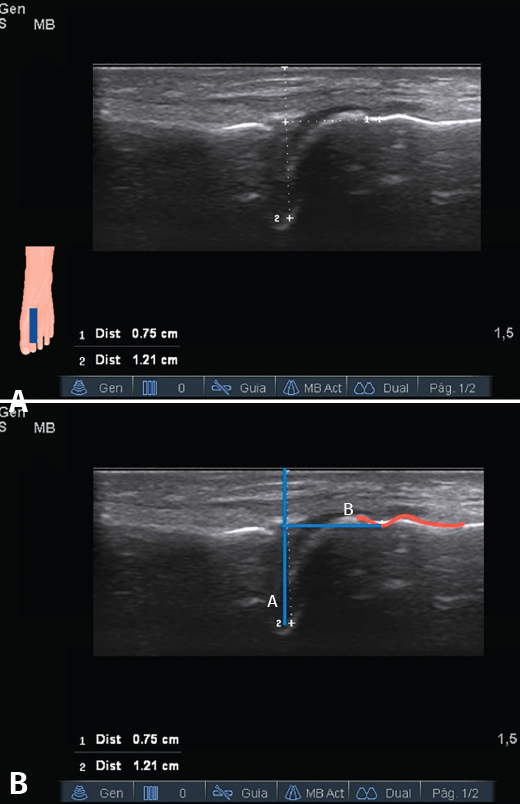

Figura 2. Medición de la distancia articulación metatarsofalángica-área dorsal desnuda. A: imagen ecográfica; B: representación esquemática. En rojo el relieve del área dorsal desnuda y la giba dorsal. En azul la interlínea articular y la distancia medida.

Para la identificación de las variables se utilizó un ecógrafo M-Turbo® Ultrasound System, con un transductor plano lineal HFL50x® (Sonosite, Fujifilm, Tokio, Japón), con un rango de frecuencia de 6-15 MHz. Con el paciente en decúbito supino, se colocó el tobillo en flexión plantar y la articulación MTF en posición de flexoextensión media. Se inició el estudio en el plano longitudinal, con el transductor paralelo al eje metatarsiano y se registró la visualización o la ausencia de visualización de cada una de las variables previamente descritas (Figuras 1 y 2), excepto la identificación del paquete vasculonervioso, que fue llevada a cabo mediante ecografía Doppler en el plano transversal. Cada una de las imágenes en las que el cirujano es capaz de identificar las estructuras se guardaron en un archivo de imágenes que posteriormente fue analizada por el radiólogo para establecer la variabilidad interobservador. La medición de la distancia interlínea articular-área dorsal desnuda y la identificación del paquete vasculonervioso fueron llevadas a cabo por el propio radiólogo en cada uno de los voluntarios sin basarse en las imágenes estáticas tomadas por el cirujano. El cirujano repitió la misma exploración ecográfica en cada uno de los voluntarios en días no consecutivos para analizar la concordancia intraobservador.

La distancia media entre la interlínea articular y el área dorsal desnuda fue de 6,2 mm (± 0,9; 3,9-9,2). El CCI inter- e intraobservador fue de 0,95 (0,93-0,96; p < 0,001) y 0,93 (0,91-0,95; p < 0,001), respectivamente. Los gráficos de Bland-Altman se muestran en las Figuras 3 y 4. No se encontraron diferencias estadísticamente significativas entre ambas mediciones, siendo la diferencia media interobservador de 0,02 (± 0,29; −0,024-0,067; p = 0,36) e intraobservador de 0,04 (± 0,33; −0,011-0,092; p = 0,13).

En cuanto a la distancia interlínea articular-área dorsal desnuda, es una medida arbitraria y la consideramos más sensible a la variabilidad al tratarse de una variable cuantitativa continua. Se define, igualmente, mediante referencias óseas, lo que facilita su identificación e influye, presumiblemente, en su concordancia casi perfecta entre las observaciones. Aunque no es un parámetro clínico y, por lo tanto, no podemos considerar qué diferencia entre las mediciones es clínicamente relevante, los diagramas de Bland-Altman muestran una distribución homogénea de las diferencias a lo largo de todo el rango de valores, con diferencias medias tan pequeñas como 0,02 y 0,04 mm, y una probabilidad del 95% de encontrar cualquier diferencia entre mediciones con un intervalo de ± 0,29 y ± 0,33 mm para el análisis inter- e intraobservador, respectivamente.